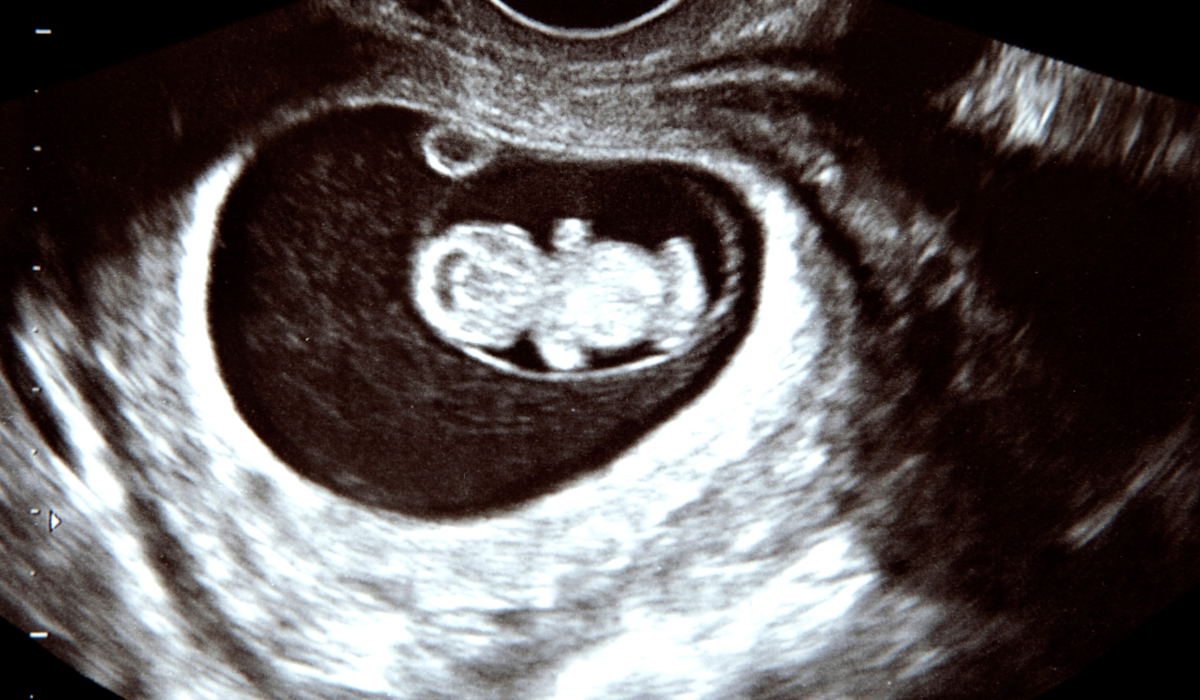

| 부인과 초음파 | 자궁과 난소의 상태를 확인하는 영상 검사 |